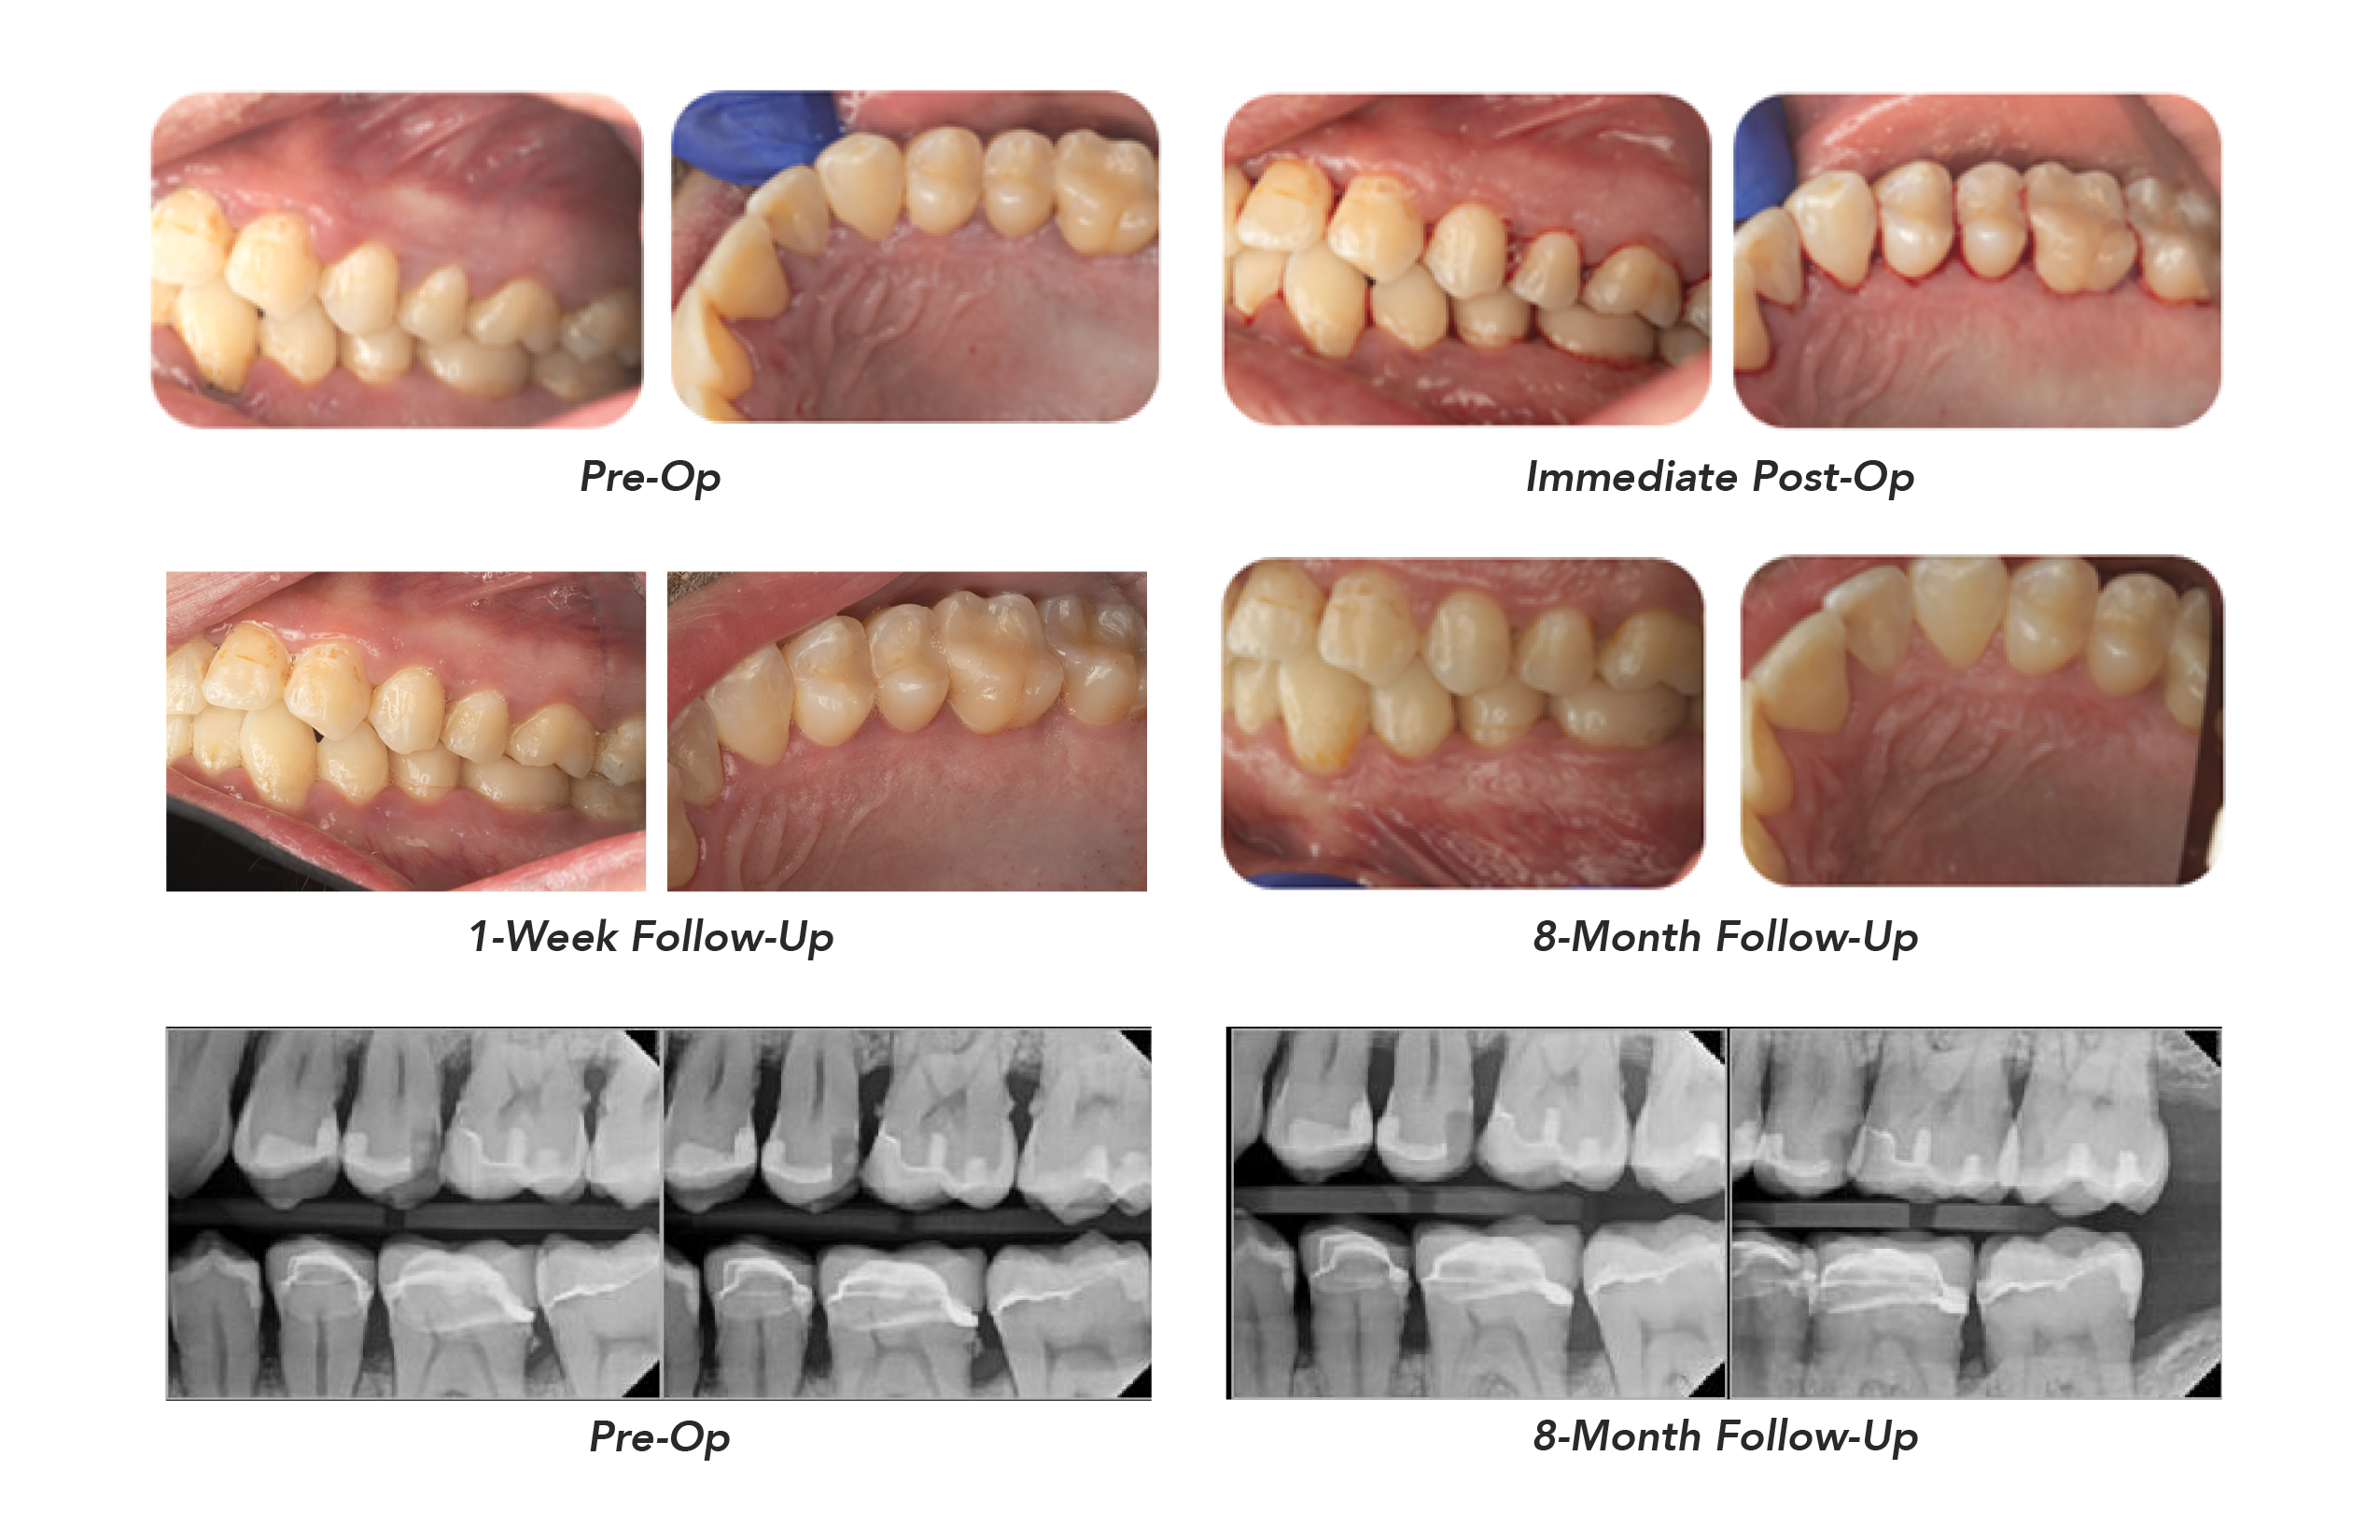

Periodontal Pocket Reduction & Resolution of Bleeding Following Solea Perioguide

Eight-month follow-up revealed notable improvements in periodontal health following Solea treatment. Reduction in pocket depths and inflammation is evident in the post-treatment charts. A 100% reduction in bleeding in the upper quadrant and more than an 85% reduction in the lower quadrant was observed. Teeth presenting persistent bleeding have restorative work that needs to be replaced.

This case demonstrates the effectiveness of Solea Perioguide for the management of periodontitis. Within 8 months, the patient exhibited dramatic improvements in pocket depth, inflammation, and bleeding. Treatment was comfortable, healing was rapid, and patient satisfaction was high. Solea Perioguide represents a minimally invasive, predictable, and patient-friendly approach to periodontal therapy compared to traditional surgical methods.